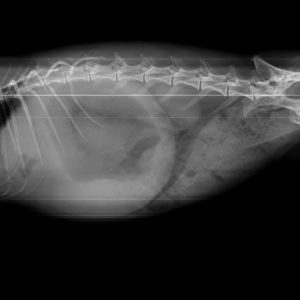

El diagnóstico por imagen es una herramienta fundamental en la medicina veterinaria moderna, ya que permite evaluar de forma precisa y no invasiva las estructuras internas del paciente. A través de técnicas avanzadas como la radiografía digital y la ecografía, es posible identificar alteraciones anatómicas y funcionales que facilitan un diagnóstico temprano y un manejo clínico más eficaz.

Nuestro servicio en Mastervet está orientado a ofrecer estudios de alta calidad, con equipos actualizados y protocolos adaptados a cada caso. Realizamos evaluaciones completas que incluyen la interpretación detallada de las imágenes y la emisión de informes clínicos claros, contribuyendo a la toma de decisiones terapéuticas.